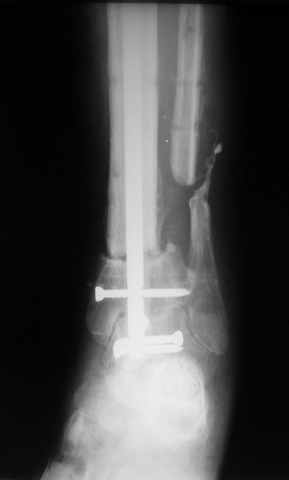

Больному выполнена резекция малоберцовой кости, ВХО раны, сближение отломков. Резекция м\б через отдельный разрез. После ВХО компрессия в аппарате, края раны сближены наводящими швами (без натяжения).

В случае гладкого заживления раны, при условии положительного решения вопроса с металлом, планируем перемонтаж аппарата Илизарова, дополнительную резекцию дистального отломка, выведение полокости голеностопного сустава в правильное положение (см. боковую Р-грамму), одномоментно остеотомия большеберцовой кости. После восстановления длинны голени, по всей видимости, артродез голеностопного сустава.

Рентгенограммы прилагаются. Фото местного статуса выложу в ближайшее время.

Мы обычно не фиксируем малоберцовую кость. Просто стараемся сопоставить ее концы за счет хорошей репозиции. В представленном случае имеется некоторое смещение дистальных фрагментов кнаружи, и, как мне кажется, ротация их вместе со стопой кнутри (ротация хорошо заметна на прямом снимке по форме таранной кости и на боковом по соотношению отломков малоберцовой). Если это действительно так, то это несложно сейчас постепенно устранить в аппарате. И тогда концы малоберцовой кости будут находиться поближе друг к другу.